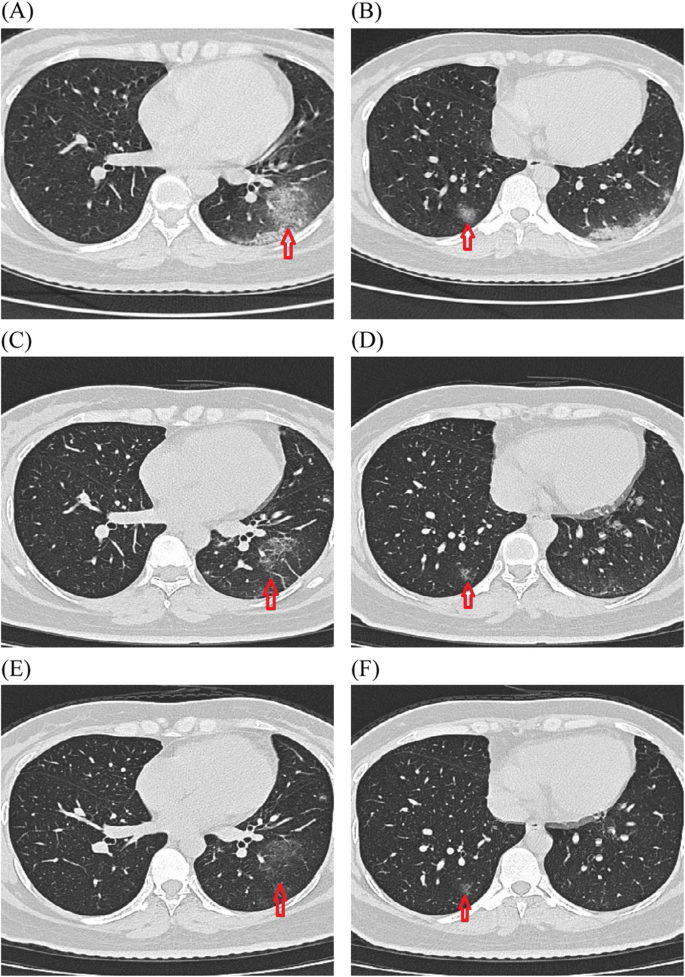

Transverse chest computed tomograms from a patient, showing ground glass opacity and consolidation of lower lobe of right and left lung on day 1 after negative for SARS-CoV-2 (a and b), on day 10 after negative for SARS-CoV-2 with absorption of 60–70% (c and d), and on day 16 after negative for SARS-CoV-2 with absorption of 80–90% (e and f)

The most common CT imaging manifestations were ground-glass opacities (51.6%, 16/31) and fibrous stripes (54.8%, 17/31) (Table 6 and Supplementary Table 1). Twelve of the 31 patients underwent repeated chest CT scans after negative nucleic acid test results; of them, seven patients (58.3%) exhibited a > 60% reduction in the ground-glass opacities. However, a reduction < 5% was observed in four patients. In case 17, the ground-glass opacity with a reduction of < 5% persisted for almost month. In addition, the 12 patients with negative throat swabs (case nos. 38–47, 49, and 50) occasionally had repeated positive fecal tests (Table 7 and Supplementary Table 2).